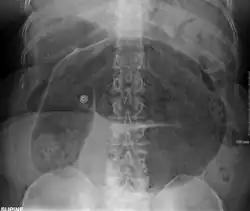

Coffee bean sign in a person with sigmoid volvulus